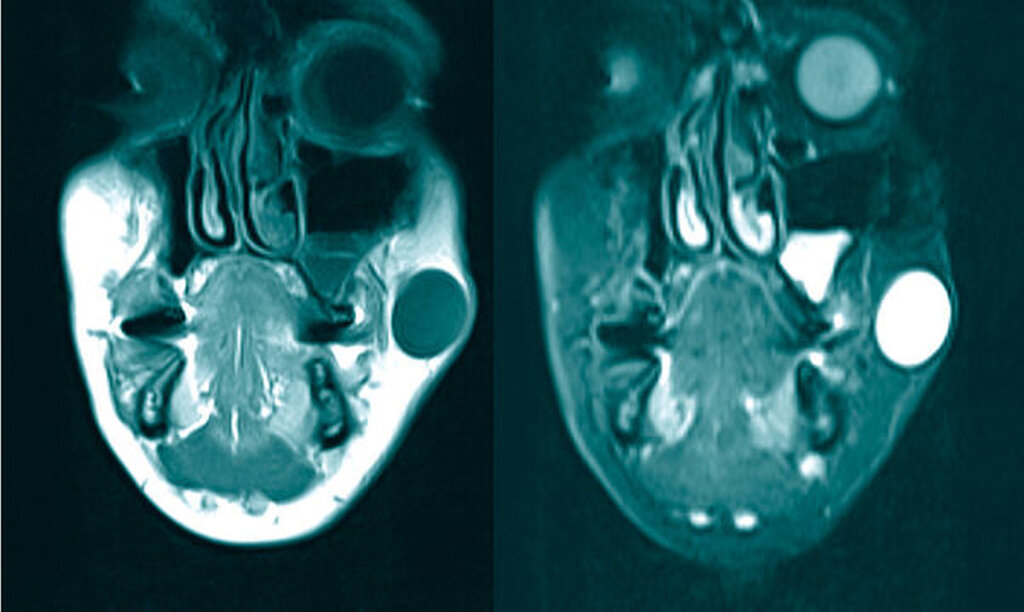

Zur weiteren differenzialdiagnostischen Abklärung wurde die Indikation zur Magnetresonanztomografie gestellt. Hier zeigte sich in der T2-Wichtung die Raumforderung als hyperintense, ovale und deutlich abgrenzbare Struktur. Dementsprechend war in der T1-Wichtung eine hypointense Struktur darstellbar. Der Befund war auf Höhe des linken Ramus mandibularis, lateral des M. masseter lokalisiert (Abbildung 2).

Differenzialdiagnostisch ist es meist erst nach Exzision und einer pathologischen Aufarbeitung möglich, die Epidermalzyste – das echte Atherom – von der Trichilemmalzyste zu unterscheiden. Klinisch kommen jedoch zahlreiche weitere Befunde der Haut und der Unterhaut infrage. Hierunter fällt auch das im vorliegenden Fall differenzialdiagnostisch abzugrenzende Lipom – ein benigner Tumor des subkutanen Fettgewebes, der sich klinisch ebenfalls prall-elastisch, verschiebbar und mit guter Abgrenzung darstellt. Oft ist eine Lappung der Lipome zu beobachten. Aufgrund des ähnlichen klinischen Erscheinungsbildes von Atherom und Lipom kann die Magnetresonanztomografie aufschlussreich sein: Der Atheromkörper zeigt sich in der T2-Wichtung aufgrund des hohen Flüssigkeitsanteils hyperintens, während das Lipom deutlich hypointens darstellbar ist. Sonografisch ist die Abgrenzung des Befunds vom Umgebungsgewebe nicht so deutlich erkennbar wie bei einem Atherom. In Anbetracht der Lokalisation der Raumforderung war zunächst auch ein pleomorphes Adenom der Glandula parotidea nicht auszuschließen. Eine maligne und relevante Differenzialdiagnose ist das zystische Basalzellkarzinom, das sich durch eine knotige Struktur und Teleangiektasien auszeichnet [Rassner, 2006].